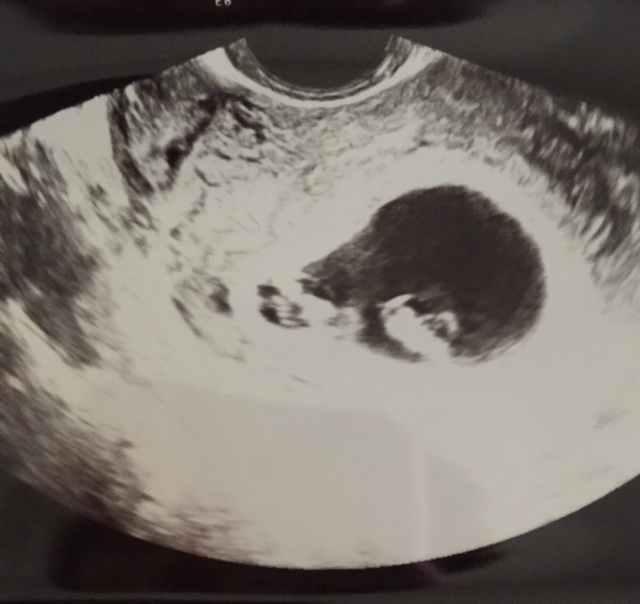

Had aother ultrasound today! Babies are measuring 9 weeks and growing good they really think they are mono di now. And one of them is sideways. So 3 pix. One is twin a and b seperate and the one with them together but not in the same position. U only see the side head viewish. Strong heart beats 179 and 181 *grow grow babies grow grow* doing the genetics blood test next week which, since they are identical, should tell us the gender! Yay

i was all worried going in, and got so emo when I heard their heart beats as always. The little nubs for hands and legs are there. One of them was wiggly a little too!